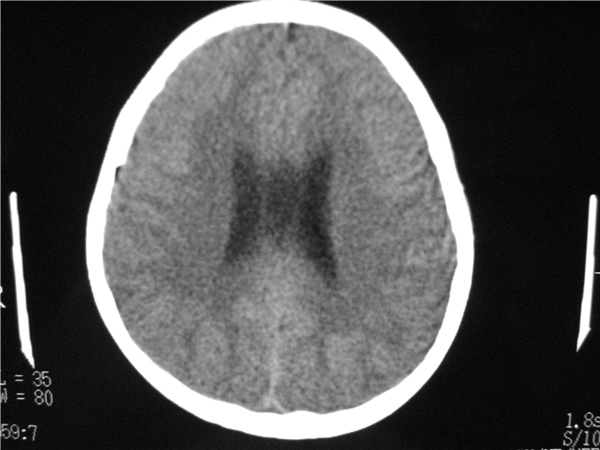

以下是引用随光逐影在2009-8-1 14:17:00的发言:[br]透明隔囊肿与vergae腔并存。

以下是引用zjzjr在2009-8-1 14:51:00的发言:[br]五、六脑室形成。